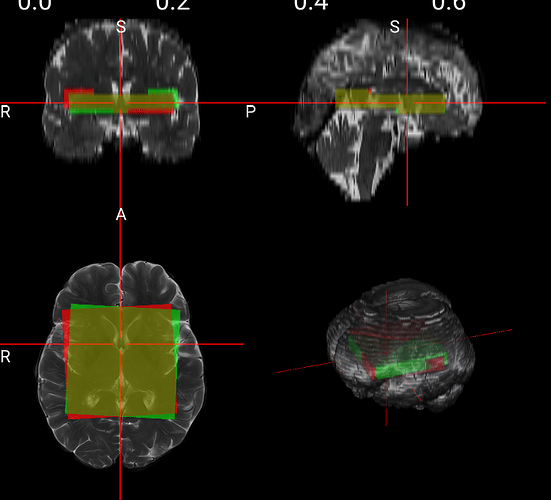

This is how it looks

According to the image from the scanner, the upper left corner should appear higher, but in my printouts the upper left is higher. I also added the flipped (row-wise down) mask as an overlay (green). I think it should appear like this.